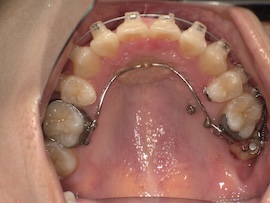

そして1ヶ月後、

左上の親知らずとその手前の歯の間に隙間があり、今は食事のたびにものが詰まります。

その隙間を閉じつつ左側の噛み合わせをより良くするため、再度ゴムかけをすることになりました。

写真にはないですが今回は左上の3番目(犬歯)と左下の7番目(一番奥)にゴムをかけます。以前左下は6番目でゴムかけをしていたのでさらにかけるのが難しくなりましたが、それでもやはりすぐに慣れるものです。

あとは正中(上下の前歯の真ん中)が合うようにも、最後のゴムかけをあと数ヶ月頑張ろうと思います。